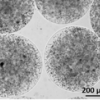

Purtroppo l’attuale terapia farmacologica per l'Huntington non consente ancora di rallentare il decorso della malattia. Nello studio sperimentale appena pubblicato sono state sfruttate le proprietà immunomodulatorie, antiinfiammatorie e trofiche di una particolare cellula del testicolo del maiale, la cellula di Sèrtoli, che normalmente svolge, nella sua sede fisiologica, funzioni nutritizie e protettive sulla spermatogenesi. Cellule di Sertoli ottenute da un allevamento di suini tenuti in condizioni di assoluta assenza di agenti infettivi sono state immobilizzate all’interno di microscopiche capsule di alginato di sodio già approvato per uso umano. Le cellule microincapsulate sono state quindi iniettate nel cavo peritoneale (addome) di topi affetti da Malattia di Huntington.

“Le microcapsule contenenti cellule di Sertoli – dichiarano i ricercatori - agiscono come una microfabbrica biologica che dalla cavità peritoneale rilascia fattori i quali, per via sistemica, possono raggiungere le parti malate, senza la necessità di iniezioni locali nel Sistema Nervoso e senza richiedere immunosoppressione farmacologica. Due grandi vantaggi che rendono il protocollo terapeutico particolarmente promettente.”

Nella foto: le microcapsule contenenti le cellule di Sertoli utilizzate nel presente studio. Le microscopiche capsule hanno dimensioni di circa 0,5 mm di diametro.